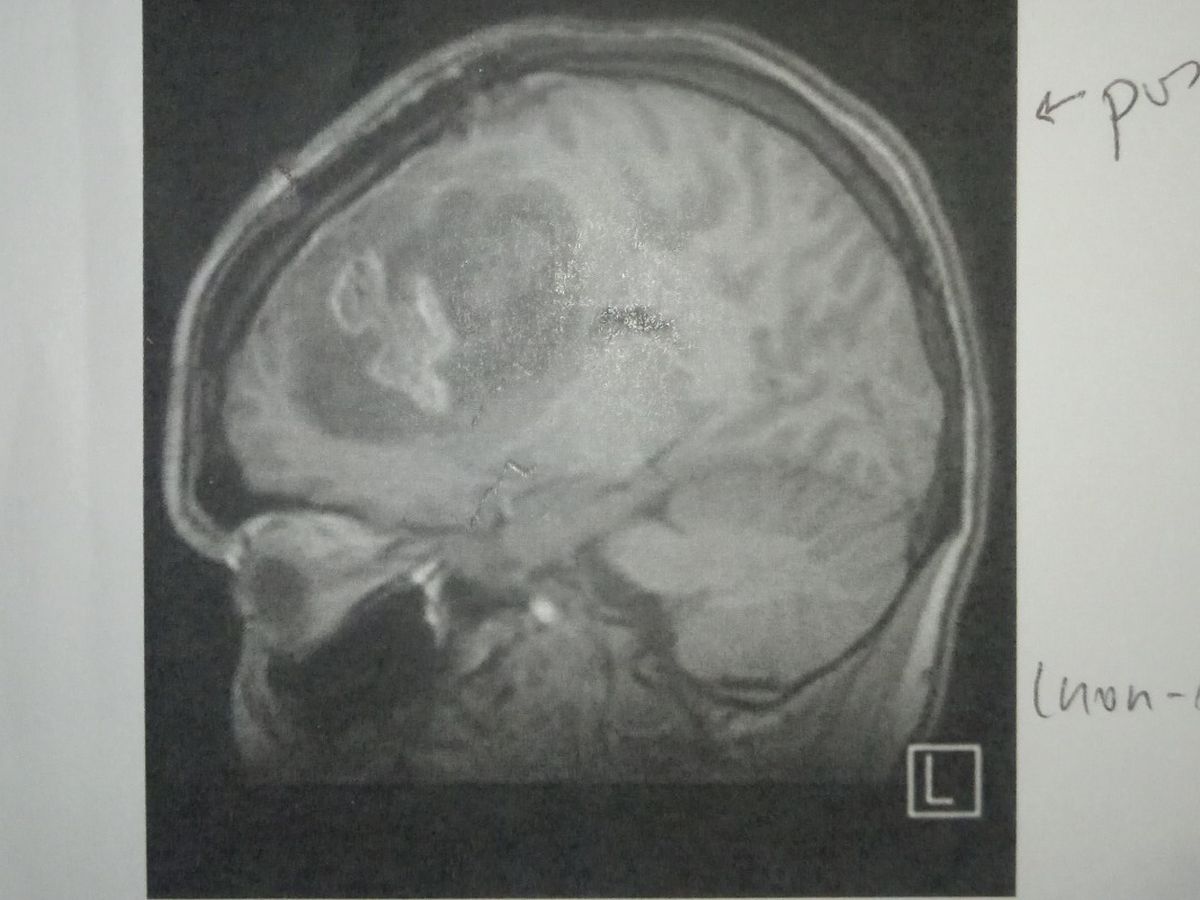

The next day, I had a brain MRI at Auckland City Hospital, and was told I had a 5x6cm tumour. After crying my eyes out, I was scheduled for a de-bulking of my tumour the following week. My mum had come over from Darwin to be with me which was amazing! I then had a meeting with my neurosurgeon, who had told me that the tumour was a stage 4 glioblastoma. So a very serious brain tumour. They scheduled me in for another operation, which was good because it had almost grown back to the same size..